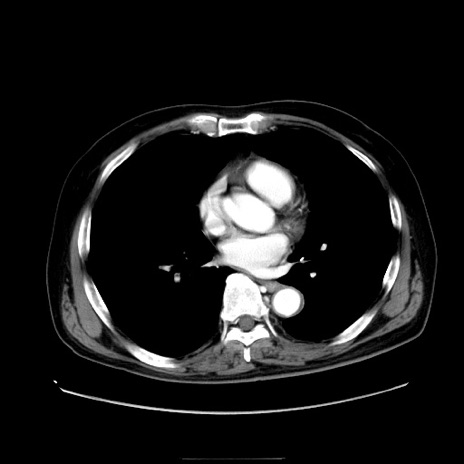

症例30(横断像)

【症例】80歳代男性

【主訴】臍周囲痛

【現病歴】約6時間前から臍下部痛が出現。次第に腹部膨隆・背部痛も生じてきたため来院。背部痛の場所は変化しない。

【身体所見】意識清明、BT 36.3℃、BP  131/87mmHg、P 87bpm、SpO2 100%(RA)、臍周囲自発痛・圧痛あり、反跳痛なし、自発痛部位に一致して板状硬あり、腹部膨隆、腸雑音減弱、CVA tenderness両側陰性。